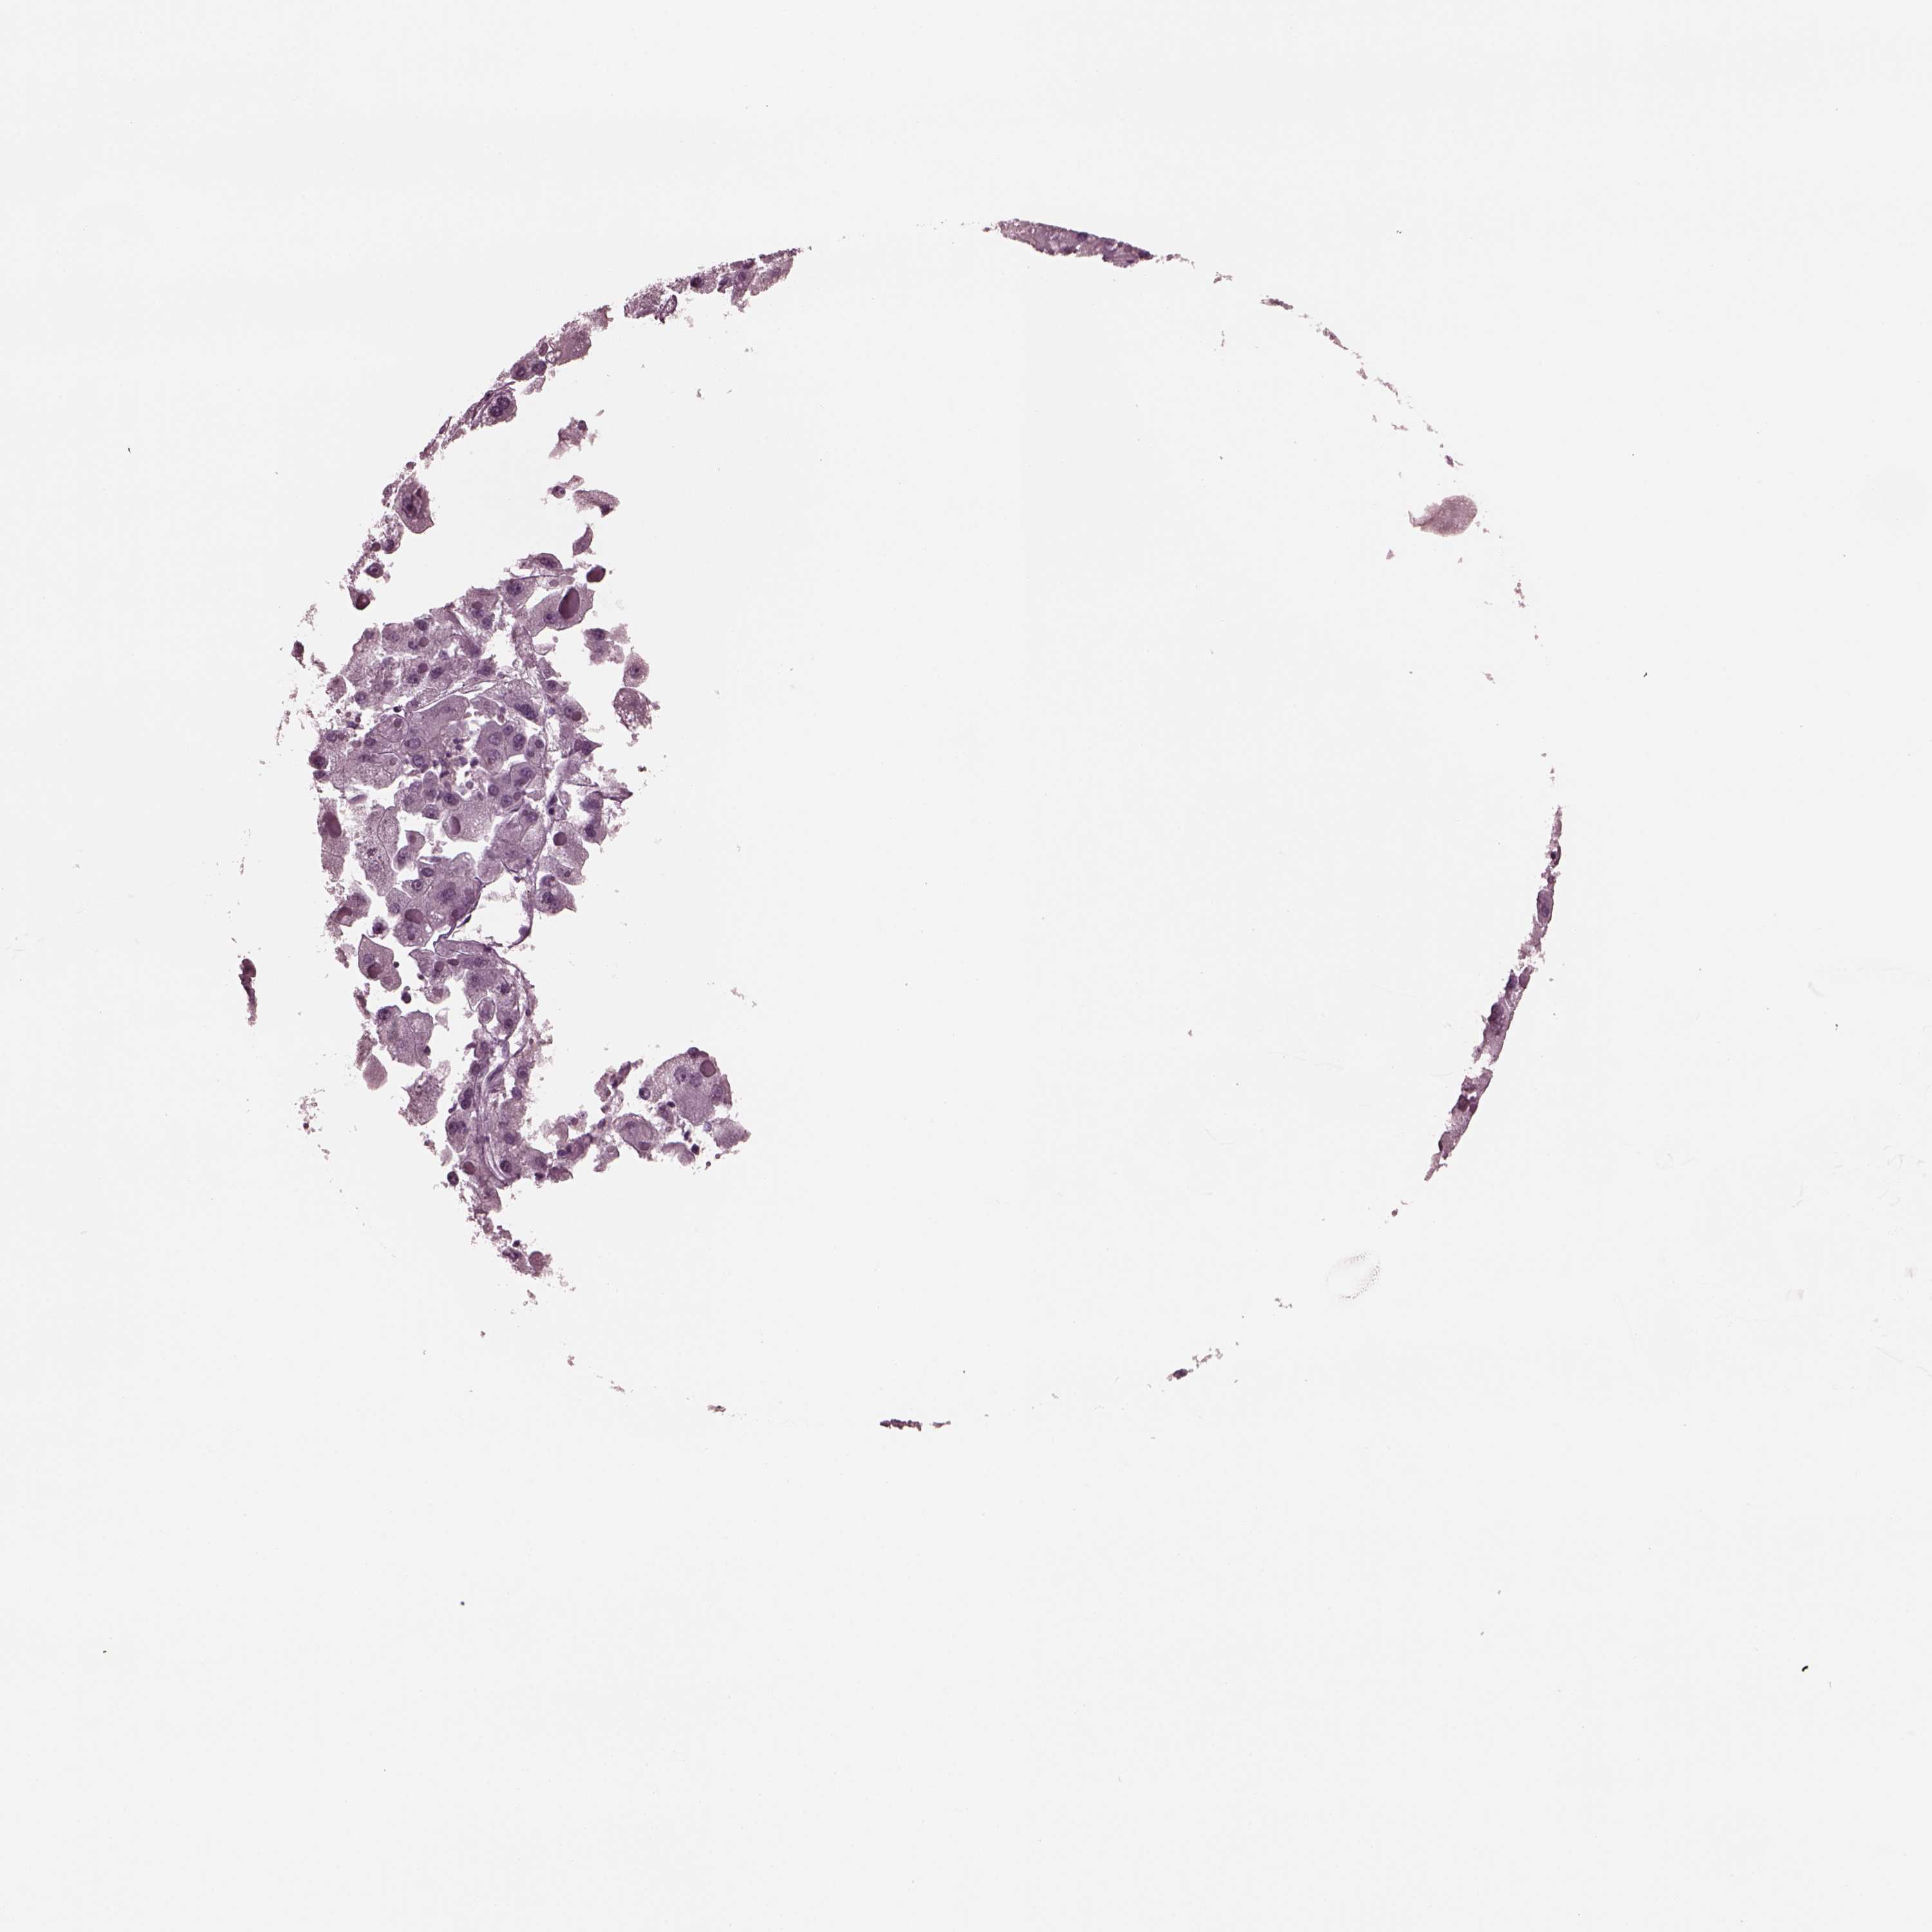

LIVER CANCER - Protein expressioni

A mouse-over function shows sample information and annotation data. Click on an image to view it in a full screen mode. Samples can be filtered based on level of antibody staining by selecting one or several of the following categories: high, medium, low and not detected. The assay and annotation is described here.

Note that samples used for immunohistochemistry by the Human Protein Atlas do not correspond to samples in the TCGA dataset.

Antibody stainingi

Antibody staining in the annotated cell types in the current human tissue is reported as not detected, low, medium, or high, based on conventional immunohistochemistry profiling in selected tissues. This score is based on the combination of the staining intensity and fraction of stained cells.

Each image is clickable and will lead to virtual microscopy that enables deeper exploration of all samples and also displays staining intensity scores, fraction scores and subcellular localization as well as patient and tissue information for each sample.

Antibody HPA029698

Antibody CAB023350

Carcinoma, Hepatocellular, NOS

Cholangiocarcinoma